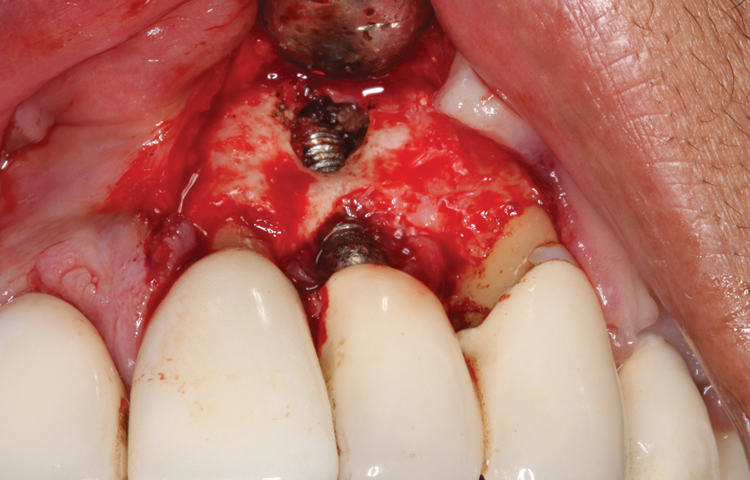

This is where the treatment became challenging. First, a curette was used to attempt to remove the granulation tissue from around the apex of the implant circumferentially. This was a difficult endeavor, especially on the palatal aspect of the site. Following curettage, an 810 nm diode laser (NV® PRO3, DenMat [alternatively: Picasso+, AMD Lasers; Gemini, Ultradent]) was used to treat the apical portion of the implant. After the laser tip was initiated using dark occlusal paper (Figure 4), it was used to debride the remaining necrotic tissue and decontaminate the entire site, reducing the bacterial count (Figure 5 and Figure 6).

(5.) The physical granulation tissue was ablated, and the entire site was decontaminated, reducing the bacterial count.

Figure 5

(6.) View of the cleaned site ready to be repaired.

Figure 6